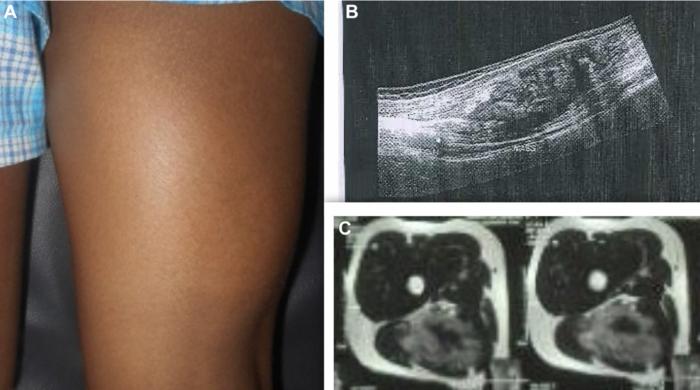

Figure 1 (A) Clinical picture, (B) Usg showing intramuscular heterogenous lesion arising from sciatic nerve, (C) MRI showing heterogeneously isointense mass measuring 12.8 × 6.6 × 3.8 cm with features suggestive of neurofibroma.

“MRI revealed a 12.8 × 6.6 × 3.8 cm lobulated intermuscular mass along the sciatic nerve. Tru-cut biopsy suggested a cellular neurofibroma.”

Imaging tests revealed a 13-centimeter mass growing between muscles and surrounding the sciatic nerve, but without affecting nearby bones. A biopsy confirmed it was a cellular neurofibroma. Despite not having access to real-time nerve monitoring equipment during surgery, the team was able to carefully separate the tumor from the nerve using magnification and microsurgical techniques. This approach helped protect the nerve fibers and maintain function. After the operation, the child experienced temporary foot drop, a condition that affects the ability to lift the foot, but made a full recovery with physiotherapy.